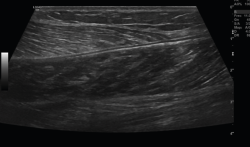

3. Músculos

Figura 11. Corte sagital de una ecografía de pierna: imagen de fibras musculares normales del gemelo.

El músculo sano, ecográficamente, presenta una ecogenicidad inferior a la del tejido celular subcutáneo y una disposición de finas líneas paralelas ecogénicas, múltiples, en cortes longitudinales, en “pluma de ave”.

Se describen 4 grados de lesión muscular: grado 0, con ecografía negativa a pesar de tener clínica sugestiva; grado 1, con hiperecogenicidad en la lesión; y los grados 2 y 3, con regiones hipoecoicas por líquido adyacente a las fibras musculares. Cuando hay cicatrización, desaparece la región hipoecoica(8)(Figuras 11, 12, 13 y 14).